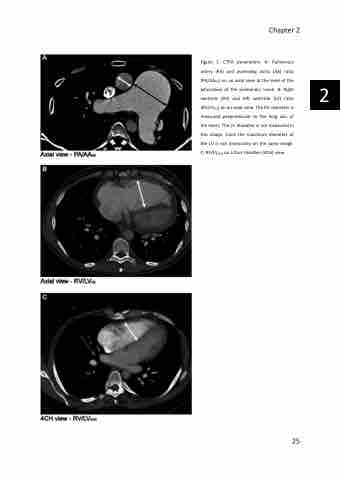

Figure 1: CTPA parameters. A: Pulmonary artery (PA) and ascending aorta (AA) ratio (PA/AAAX) on an axial view at the level of the bifurcation of the pulmonary trunk. B: Right ventricle (RV) and left ventricle (LV) ratio (RV/LVAX) on an axial view. The RV diameter is measured perpendicular to the long axis of the heart. The LV diameter is not measured in this image, since the maximum diameter of the LV is not necessarily on the same image. C: RV/LV4CH on a four chamber (4CH) view.